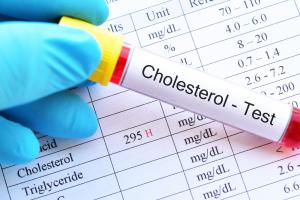

Actualité publiée le 12/07/2025MALADIE CARDIAQUE et DÉMENCE : Le mauvais cholestérol doublement responsable

Actualité publiée le 08/07/2025

DÉMENCE : Le mauvais cholestérol contribue à l’expliquer